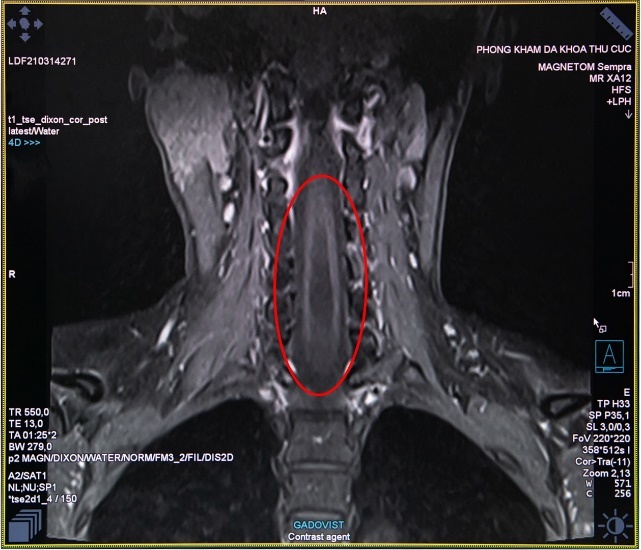

Bác sĩ chẩn đoán hình ảnh Nguyễn Chí Phồn - Phòng khám đa khoa Thu Cúc - cho biết: “Trường hợp của chị H. là chụp cộng hưởng từ MRI cột sống và tủy sống có tiêm thuốc đối quang từ, nhằm phát hiện những tổn thương thần kinh. Đây là công cụ đáng tin cậy để chẩn đoán bệnh rỗng tuỷ sống. Đối với những trường hợp nghi ngờ mắc bệnh này, nếu chỉ định chụp X- Quang hay chụp cắt lớp vi tính MSCT sẽ khó đánh giá chính xác”.

Hình ảnh thu được từ chụp cộng hưởng từ MRI tủy sống của chị H. cho thấy trong đoạn tủy sống hình thành một hốc rỗng chứa các dịch, các dịch này tích lại thành các khoang và nang hốc - biểu hiện của căn bệnh rỗng tủy. Sau khi có kết quả khám cận lâm sàng, các bác sĩ của Thu Cúc đã hội chẩn nhằm xác định căn nguyên bệnh và tìm phương pháp điều trị tốt nhất.

Hình ảnh chụp cắt lớp của người mắc bệnh tủy rỗng. |